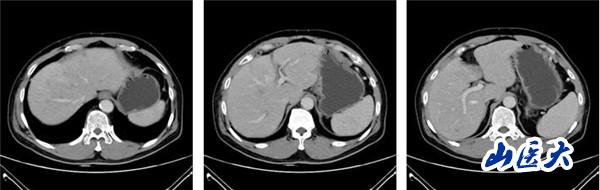

(2022-01-08基线肝脏CT静脉期)

该患者在团队成员仔细阅片、认真讨论下,因患者为PD-L1 CPS高表达人群,TMB-H基因状态。尽管目前国内外胰腺癌诊疗指南并没有对该类型患者指明个体化治疗策略,但通过查阅近年来已经报道的小样本临床研究以及个案报道资料,最终为患者制定了免疫联合化疗治疗策略:PD-1单抗+AG治疗6周期后,PD-1单抗+卡培他滨维持治疗。2022年8月26日,患者再次完善胸腹部CT评价疗效后,达到了大PR(部分缓解)的效果。多达20余处肝转移病灶几乎消失不见,患者可以正常工作生活。